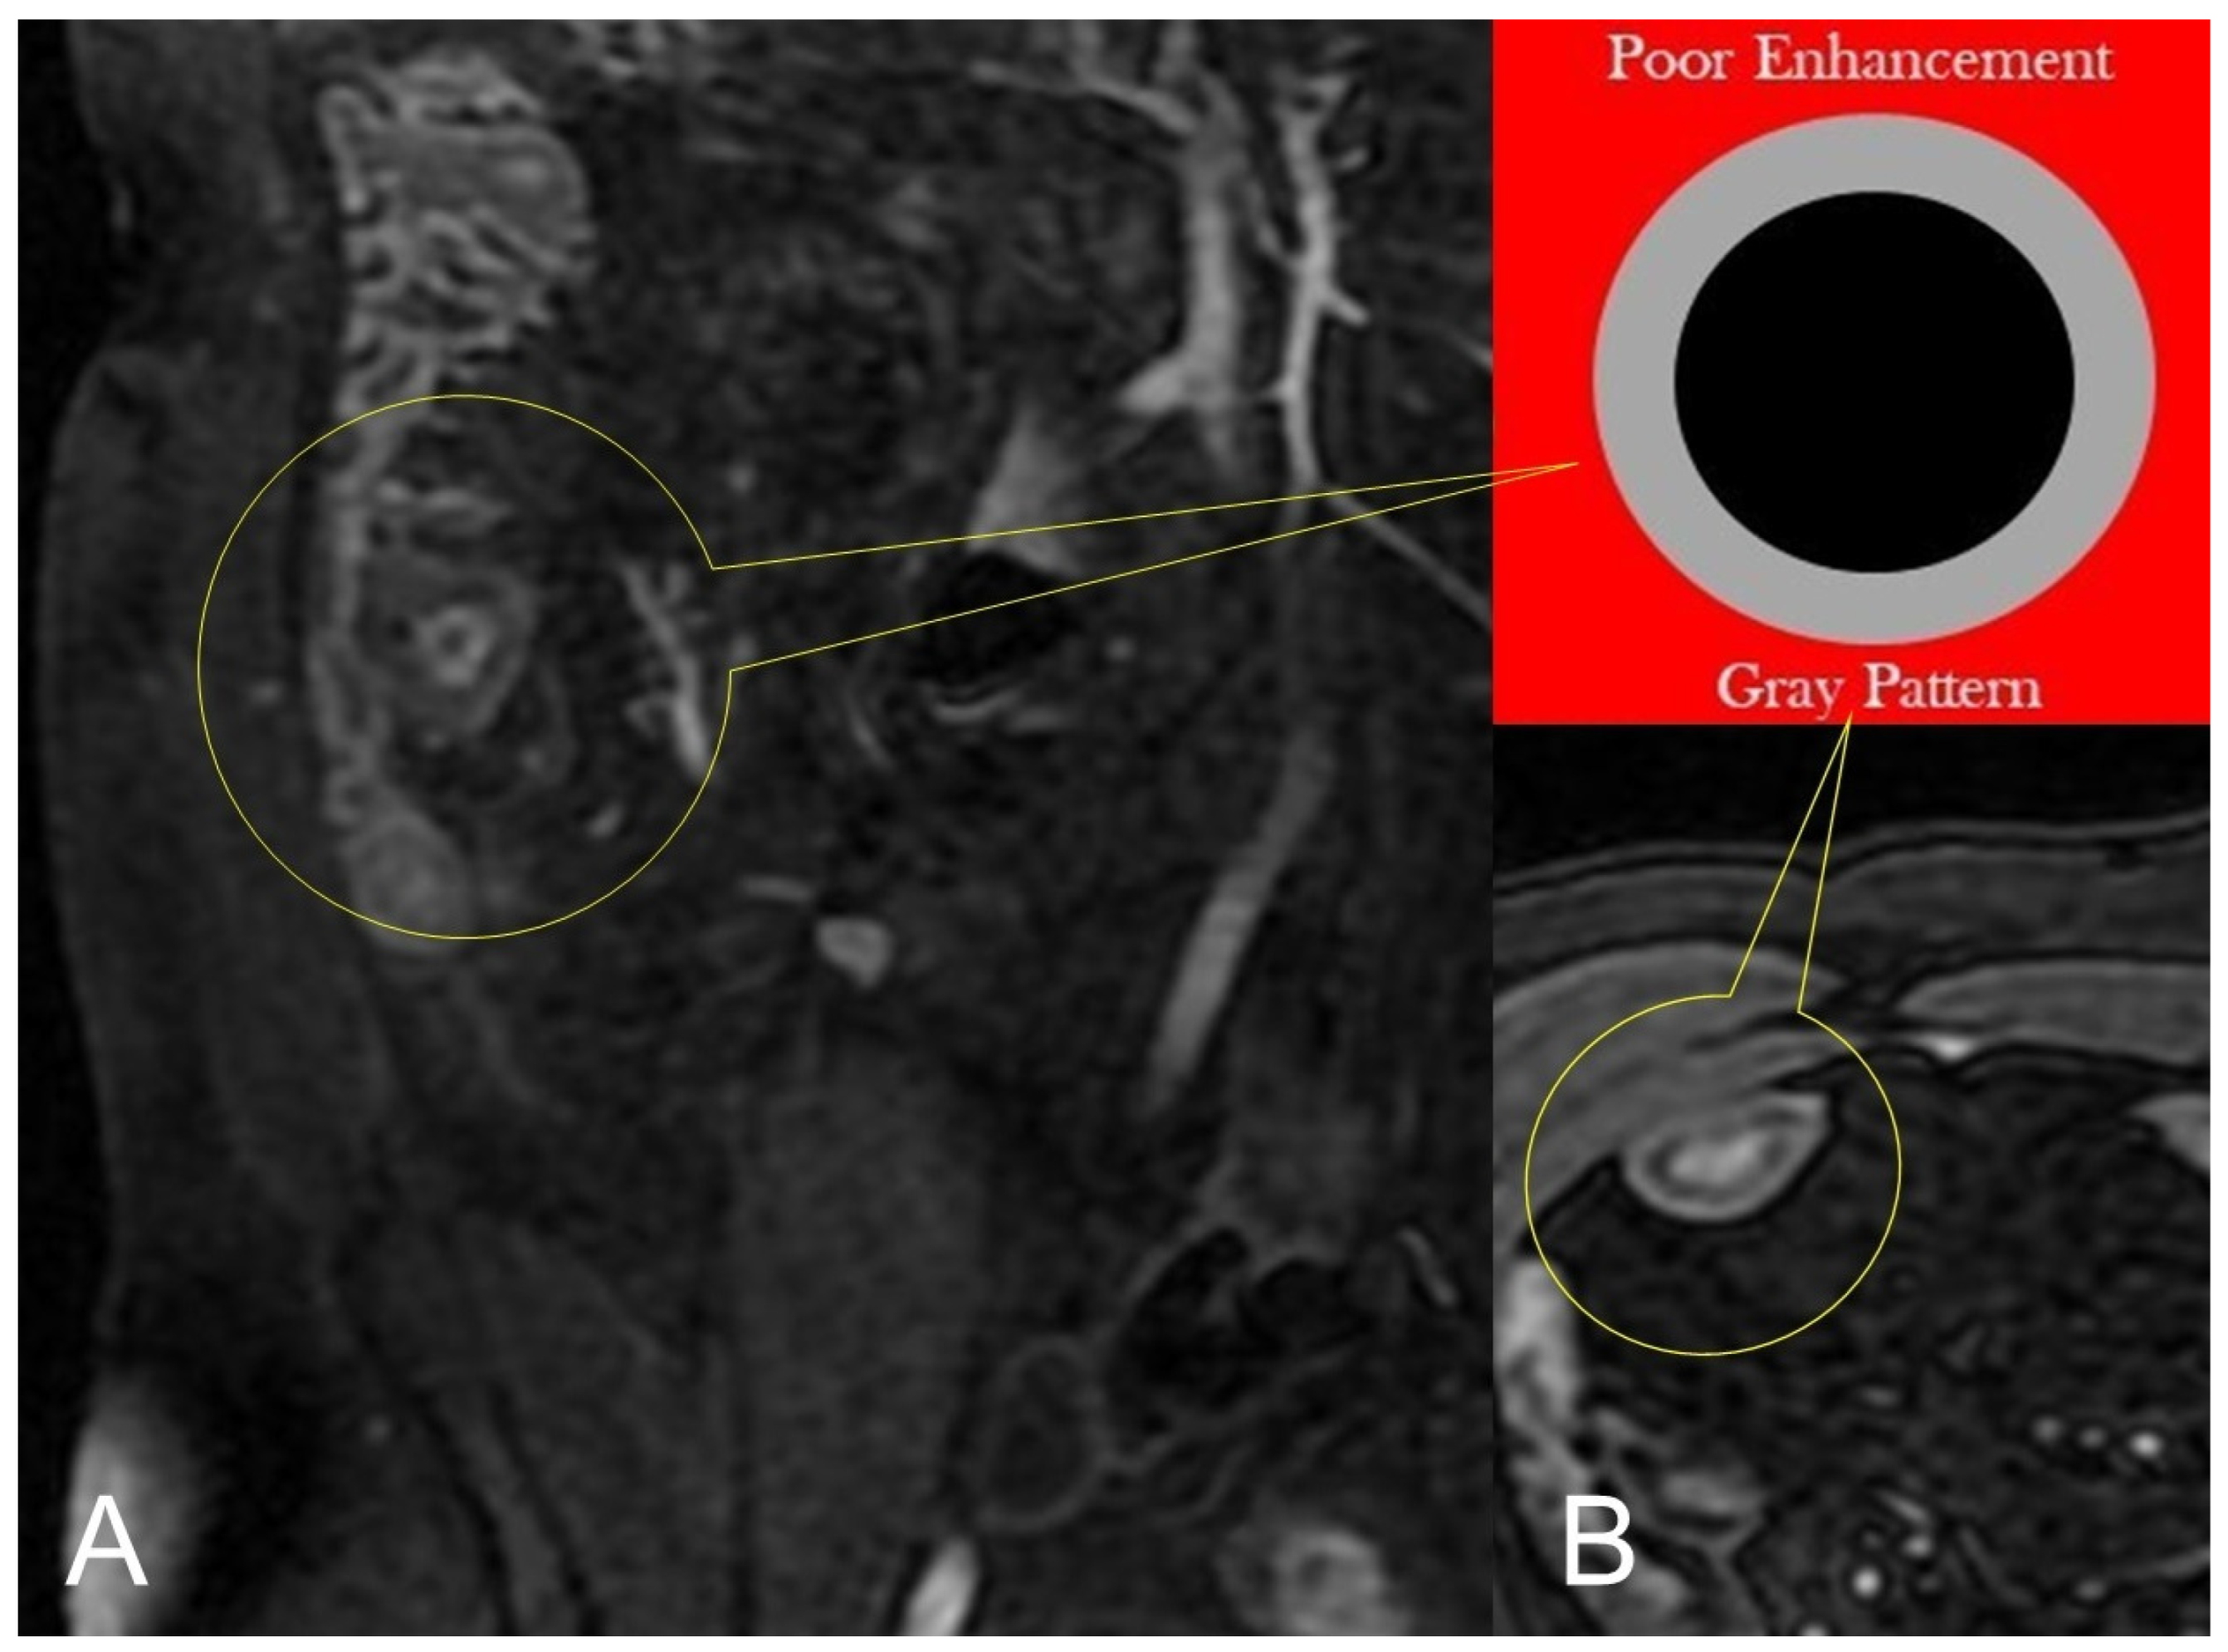

In CD, segmental bowel wall mural hyperenhancement represents the pathological tissue that at contrast-enhanced MRE is revealed as increased mural signal intensity in a small bowel’s segment compared with the normal adjacent intestinal tract [5]. Mural hyperenhancement can be asymmetric (in a small bowel loop, it could involve the mesenteric border more than the antimesenteric one), stratified (bilaminar or trilaminar inner-wall hyperenhancement or halo sign), or homogeneous (evenly distributed over the entire bowel wall). Submucosal edema, granulation tissue, intramural fat accumulation, fibrosis, or inflammatory infiltration may contribute to stratified enhancement (Figure 3 and Figure 4). Bowel wall enhancement evaluation is correctly depicted in the enteric phase (45–50 s after the intravenous contrast material injection begins) and/or in portal venous phase (60–70 s after the intravenous contrast material injection begins). Furthermore, we consider also that endoscopy and histopathological examination clearly show the absence of mucosa in the affected intestinal segments, so the term “mucosal hyperenhancement” is incorrect when the stratified enhancement pattern is expressed and should not be used. Finally, it must be underlined that the segmental bowel wall mural hyperenhancement is a sensitive but non-specific sign of CD, and therefore it must always be contextualized in the general framework of interpretation [6].

Figure 4.

Lack of layered or homogeneous enhancement can be related to fat ((B), axial FIESTA) image, or fibrosis parietal deposition, with poor enhancement and gray pattern on contrast-enhanced fat-suppressed T1-weighted image ((A), coronal image).

In chronic disease, there is a fat deposition in the submucosal layer that appears as hypo-intensity in the thickness of the intestinal wall on T2-weighted images with fat saturation (Figure 4B).

During subacute transmural inflammation, the thickened and fibrotic bowel wall exhibits diffuse and homogeneous contrast enhancement, and the mild mucosal enhancement with hypo-intensity of the deep layers suggests fibrotic condition [19].